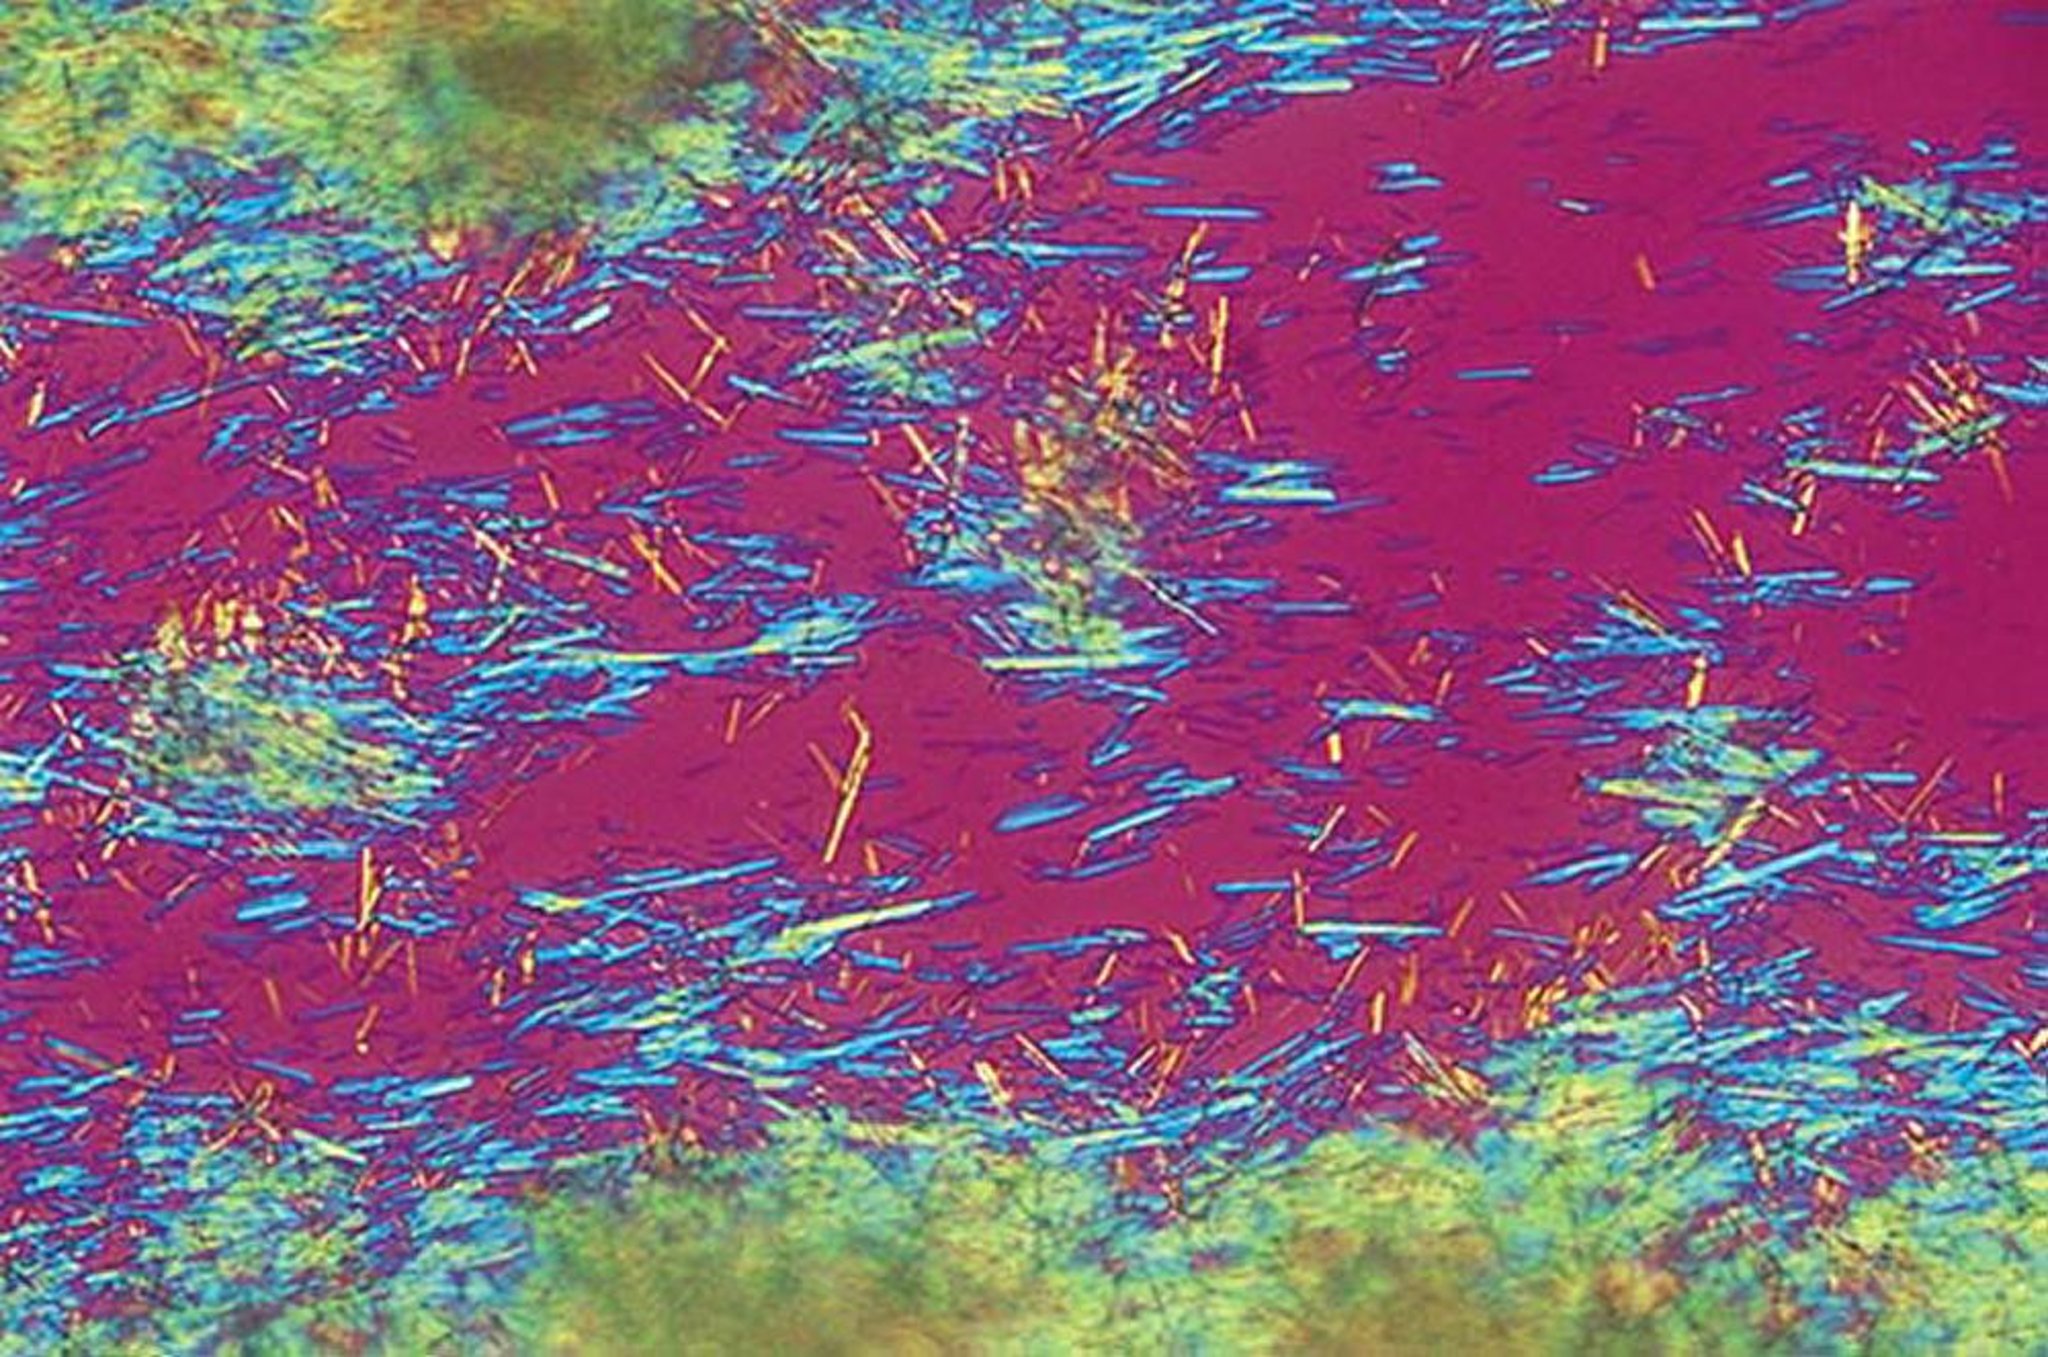

急性痛風性関節炎が疑われる場合,初診時に関節穿刺および関節液検査を行うべきである。痛風と診断された記録がある患者での典型的な再発には関節穿刺は必須とならないが,診断に疑問がある場合や,患者の危険因子または臨床的特徴から感染性関節炎が示唆される場合は,関節穿刺を施行すべきである。一部の症例では,痛風の診断は患者の病歴と臨床的特徴から,あるいは関節液を採取できない症例では画像検査の結果から合理的に推測できる場合もあるが,罹患関節から採取した滑液中でMSU結晶の存在を確認することを,あらゆる方法で試みるべきである。

関節液検査では,液体に遊離するかまたは食細胞によって取り込まれている,針状で強い負の複屈折性の尿酸結晶を同定することによって診断を確定できる。発作時に採取された滑液には炎症の特徴が認められ(の表を参照),通常は白血球数が2000~100,000/μLとなり,多形核白血球の割合が80%を超える。これらの所見は感染性関節炎とかなり重なり,グラム染色(感度は低い)および培養で感染性関節炎を除外する必要がある。